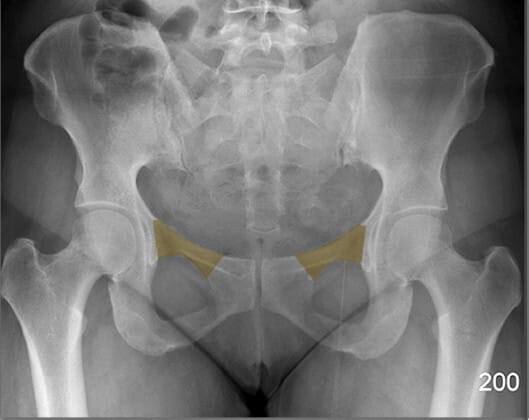

치골결합 (Pubic Symphysis)

| 치골결합 (Pubic Symphysis) |

| ✅ 치골의 정중앙에서 좌우를 연결하는 섬유연골 관절로, AP view에서 골반 중앙 하단에서 좁은 간격의 음영으로 보입니다. |

| 🔴 외상이나 분만 후 이완이나 분리(pubic diastasis)가 발생할 수 있습니다. |